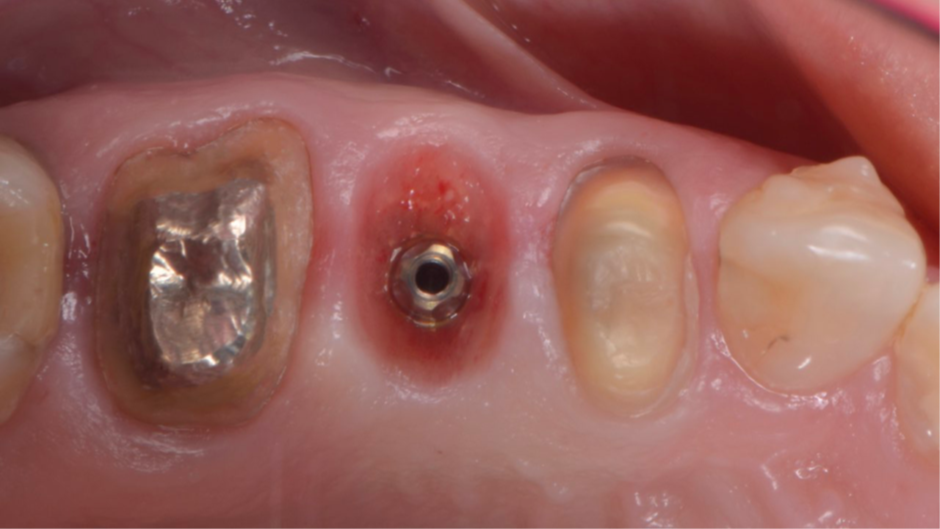

Após o planejamento virtual no programa Exoplan – Exocad (Figura 3) e confecçãode uma guia cirúrgica prototipada, foi realizada uma cirurgia guiada por computadorImplaguide 3.5/4.0 e instalado um implante Due Cone 3,5x9mm (Figura 4). Foi instalado também um cicatrizador de 3,5×2,5 (Figura 5). Após quatro meses de cicatrização, o implante estava com o cicatrizador aparente na mucosa (Figura 6).

Figura 6 – Pós-operatório de quatro meses.